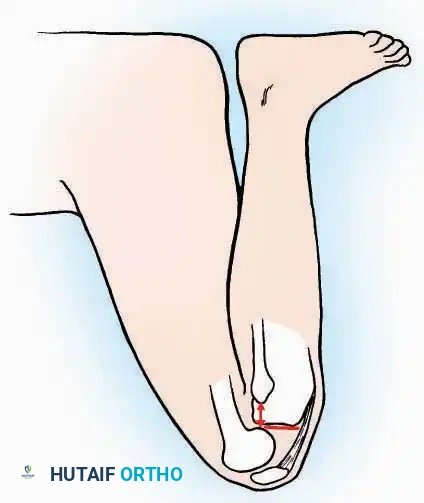

Kocher Approach (Curved L)

Indications: Complete excision of the calcaneus (calcanectomy) for malignant tumors or recalcitrant osteomyelitis.

Surgical Technique:

* Incision: Incise the skin over the medial border of the Achilles tendon, starting 7.5 cm proximal to the calcaneal tuberosity. Extend it distally to the inferoposterior aspect of the tuberosity, curve it transversely around the posterior heel, and continue distally along the lateral surface of the foot to the tuberosity of the fifth metatarsal.

* Deep Dissection: Divide the Achilles tendon directly at its insertion and carry the dissection down to the bone.

* Enucleation: To reach the superior surface, free all tissues beneath the severed Achilles tendon. The calcaneus can then be enucleated subperiosteally or extraperiosteally depending on the oncologic or infectious margins required.